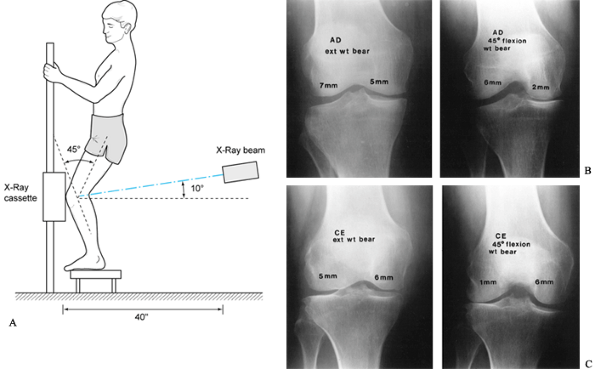

(AP), lateral, notch, and patellofemoral views. The posteroanterior

documenting degenerative changes (17); however, joint space narrowing is best noted on the PA 45° flexion weight-bearing view (Fig. 84.14) (56). A true lateral view taken at 30° of knee flexion allows for assessment

subluxation (Fig. 84.15).

Figure 84.14. A: Technique for the 45° PA flexion weight-bearing x-ray study of the knee. B: Demonstrating medial compartment joint space loss in flexion. C: Demonstrating lateral compartment joint space loss in flexion.